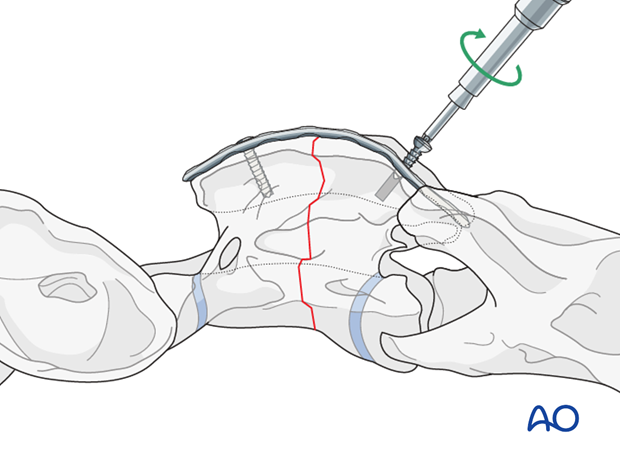

After exposing the dorsal surfaces of the atlas and axis, the alignment of the vertebrae is corrected and maintained with bone-holding forceps.

Steinmann pins are inserted in horizontal direction into the cranial and caudal fragment to facilitate the reduction

With the reduction forceps in position, the appropriately sized plate is applied on the dorsal spinous process.

One cortex screw is inserted into each fragment in load fashion. The correct length of the screws is determined with the help of fluoroscopy.